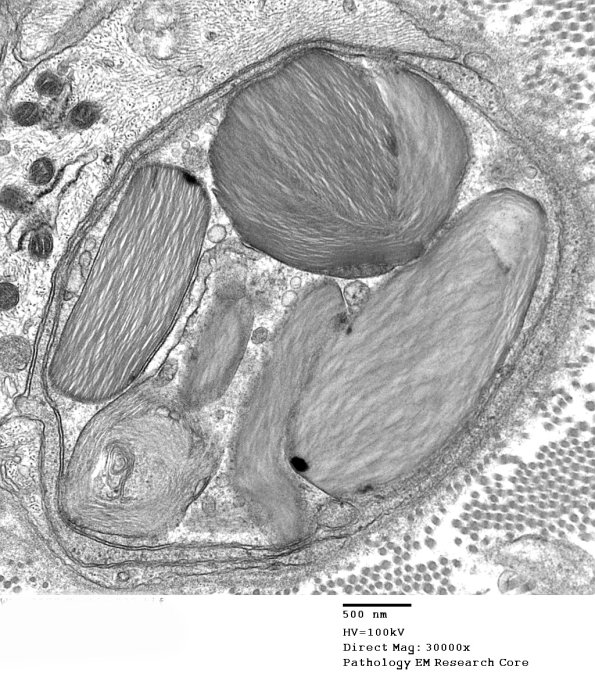

Higher magnification of image #10A1. (electron micrograph)